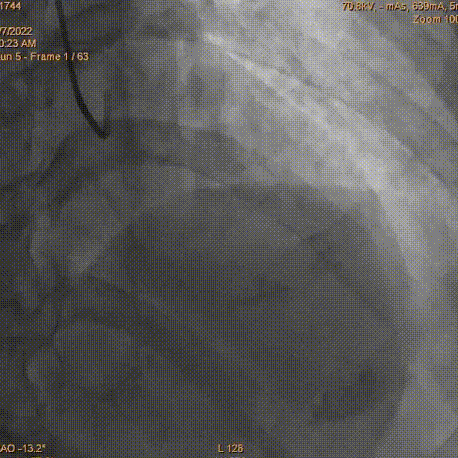

2.5×12mmSprinter球囊以12atm×5s、14atm×5s扩张RCA中远段狭窄病变